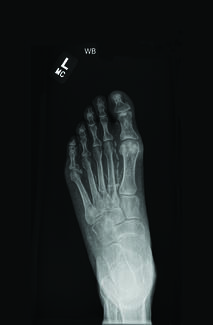

I would mention one patient in particular, which is actually quite remarkable. This gentleman, he is in his early sixties, very fit and young man, still works. He was admitted to our hospital with CLI left leg with an ulcer on the dorsal of the foot, and the big toe, and also an interdigital ulcer between the fourth and fifth toe. He was in tremendous rest pain. He couldn't sleep. He was on opioid, analgesics, still not controlled. So we did investigate him and try to do something on him. When we did a catheter angiogram on him, there was no visible named artery below the knee. You can see few color trials but they were not in the foot either.

Then everybody agreed this is fine. This is the last salve attempt to do that. So he came to my clinic, I put a neurostimulation treatment. Before I put a neurostimulation treatment, in almost every patient I try to do a pre-new re stimulation duplex scan and I have a set protocol where I record the diameter of the TBL arteries, the peak systolic velocity in those arteries, the volume flow, the ankle pressure with ABPI, and the toe pressure with TBPI. So I've done that, and a very little flow. You know can see the peak systolic velocity is probably around seven.